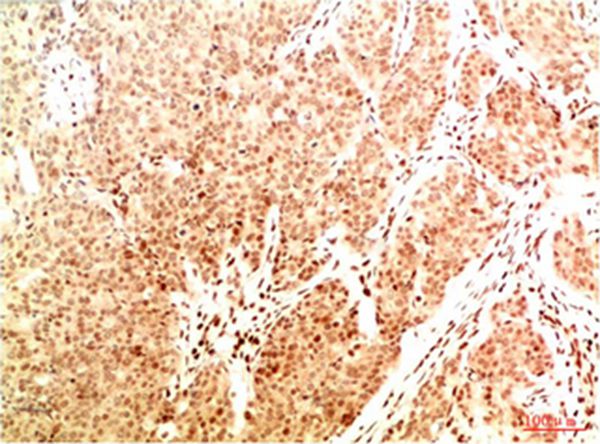

Immunohistochemical analysis of paraffin-embedded Human Breast Carcinoma Tissue using Acetyl NF kB P65(K314/K315) Mouse mAb diluted at 1:200.

Immunohistochemical analysis of paraffin-embedded Human Lung Carcinoma Tissue using Acetyl NF kB P65(K314/K315) Mouse mAb diluted at 1:200.